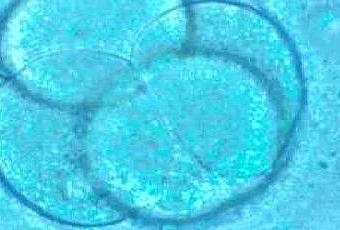

Las células que se forman tras la fecundación van a ser reconocidas jurídicamente como embrión.

El abogado general del Tribunal de Justicia de la Unión Europea (TUE), Yves Bot, dictaminó que “las células pluripotenciales, que aparecen desde la fusión de los gametos y que sólo subsisten con esta forma durante los primeros días del proceso,presentan la característica esencial de tener cada una por sí misma la capacidad de desarrollarse hasta formar un ser humano completo”.

“Dichas células, en la medida en que constituyen elprimer estadio del cuerpo humano en el que van a convertirse debencalificarse jurídicamente de embriones, cuya patentabilidad deberá excluirse”, afirma Bot.